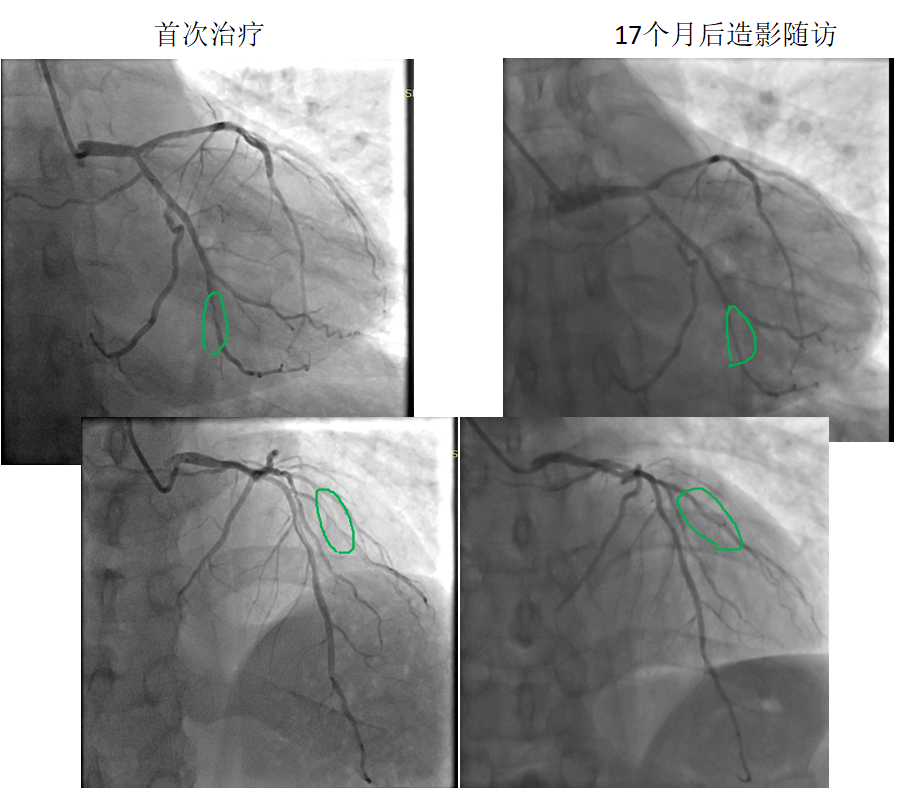

藥物球囊治療原位病變

患者:男,38歲

病變部位: OM中遠(yuǎn)段95% ;D1近段90%

使用藥物球囊:2.0 x 20mm; 2.0 x 20mm

17個月后造影隨訪:OM中遠(yuǎn)段20% ;D1近段20%

藥物球囊治療原位病變(圖1)